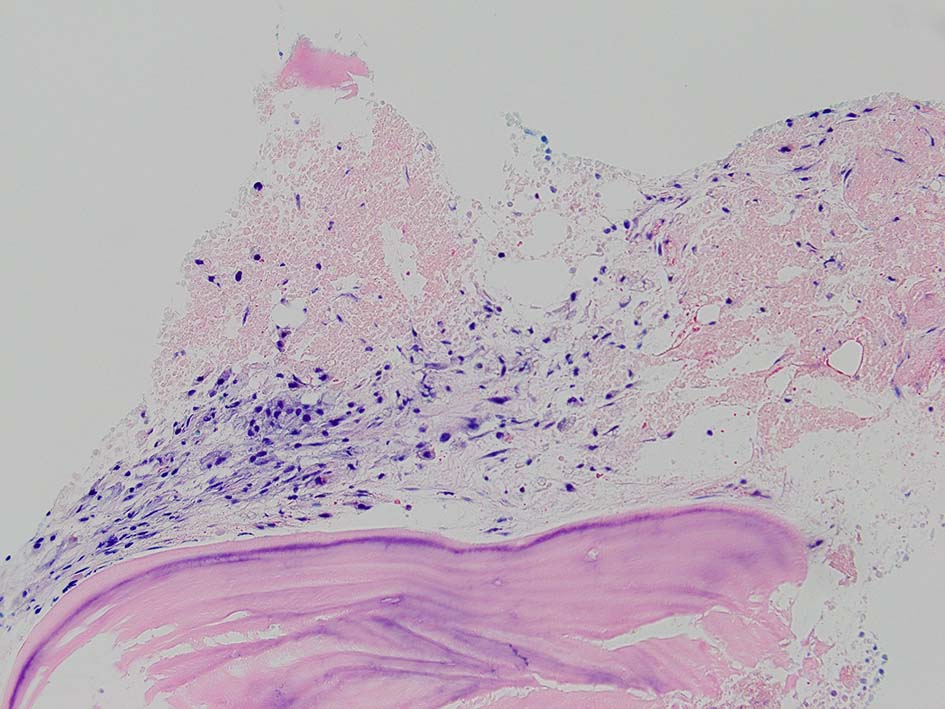

骨髄生検組織所見

骨髄生検組織では骨梁間に壊死に陥った細胞の凝固壊死像が確認できる. 本例では脂肪細胞は消失せず形態が残っている.壊死のあとには, 髄腔に線維化をきたす. 上図には線維化を示し, 右端の図では壊死巣と線維化の境界が観察される.

本例ではviableな腫瘍細胞がハーバース管と考えられる管内に認められた.(髄腔とハーバース管腔は解剖学的に同じ場所といえるのか?)

ハーバース管は緻密骨内の骨構造であり, 管内には動静脈, 脈管周囲リンパ管, 神経線維が入る. 解剖学的に海綿骨骨髄腔とは異なる空間構造と考えられる.--viableな腫瘍細胞の存在はリンパ管、血管内への腫瘍浸潤と考えられる.